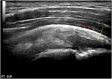

The rotator cuff is a group of four muscles and tendons surrounding the shoulder joint providing it strength and stability. The rotator cuff consists of the subscapularis, supraspinatus, infraspinatus and teres minor. Many shoulder complaints are caused by rotator cuff pathology such as impingement syndrome, tendon tears and other diseases e.g. calcific tendonitis. Diagnosis starts with clinical history and physical examination, after which imaging is often used to help confirm clinical findings depending on the differential diagnosis. The aim of the article is to review the frequently used imaging modalities to assess the rotator cuff and cuff-related disease, specifically focusing on radiography, ultrasonography and magnetic resonance imaging. This article will outline the advantages and disadvantages for each modality and illustrate typical radiological findings of common rotator cuff pathologies.